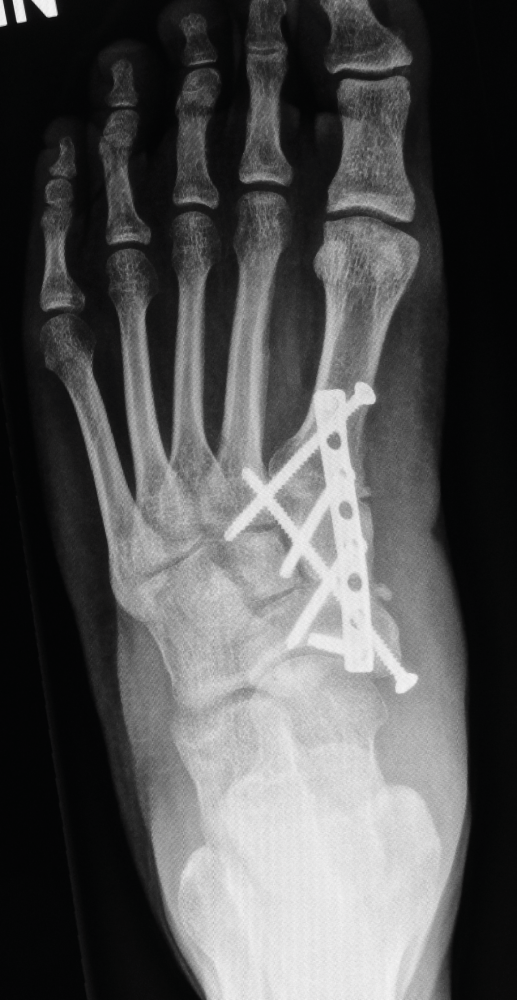

Röntgenkontrolle

Die Kontrollaufnahmen unmittelbar nach dem Eingriff zeigen die anatomisch korrigierte Fußform. Die eingebrachten Schrauben stützen den Aufbau so lange bis der Knochen vollständig verheilt ist.